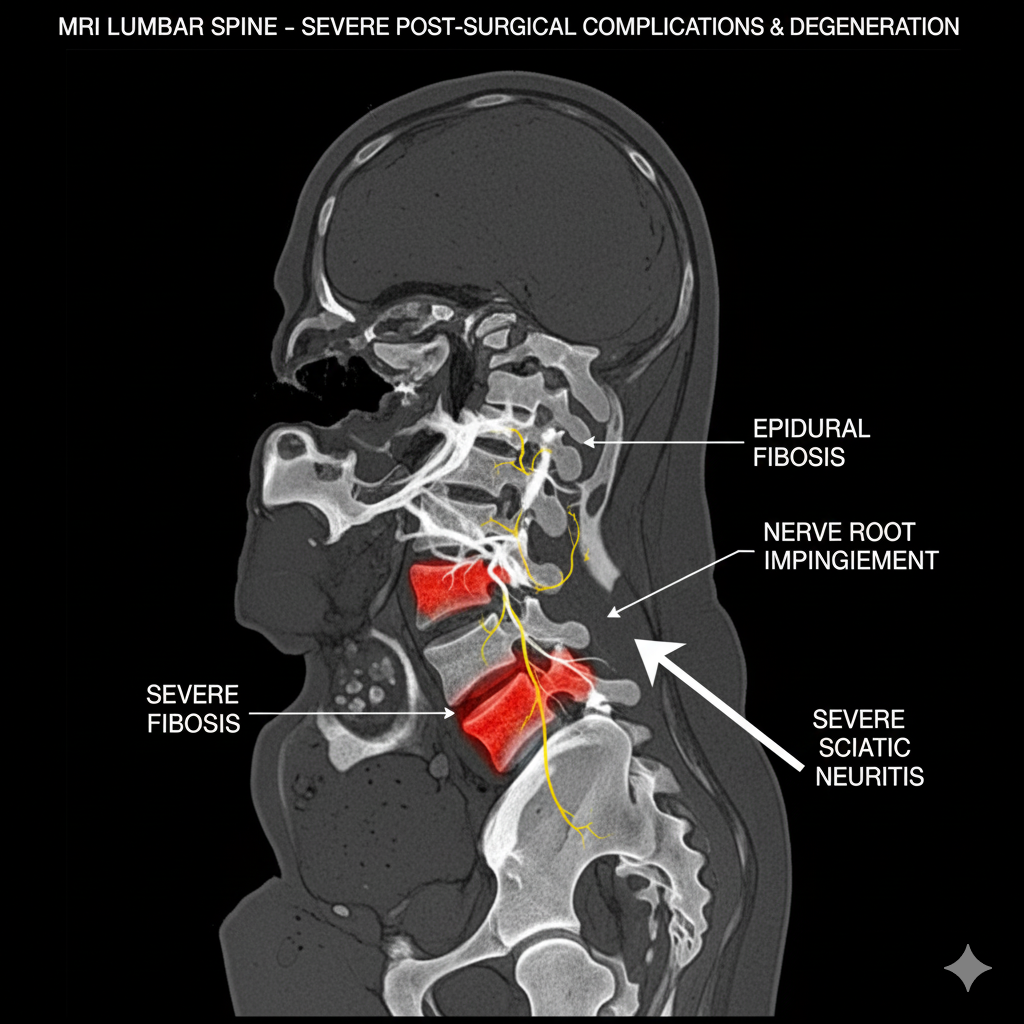

It was devastating — but after reviewing my MRI results, the doctor concluded that I needed spinal surgery to fix what they called “severe disc degeneration and nerve compression.” The inflammation had already started to affect nearby muscles and nerves, and they warned me that waiting too long could cause permanent nerve damage.

I was told that if I didn’t act fast, I could lose mobility in my legs — or even end up unable to walk properly. The idea of losing control over my own body terrified me.